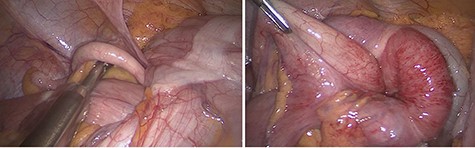

The patient was urgently taken to the operating room with a pre-operative diagnosis of colon intussusception and underwent laparoscopy. Intra-operatively, colocolic intussusception was present. The cecum was found to be the intussusceptum, subsequently telescoping far into the transverse colon that was found to be the intussuscipiens (Fig. 3).

Intra-operative finding of the intussusception. (Left) The terminal ileum and the appendix were pulled like a tail by the intussusceptum into the intussusception. (Right) The cecum was identified as the intussusceptum, telescoping into the transverse colon that was identified as the intussuscipiens.